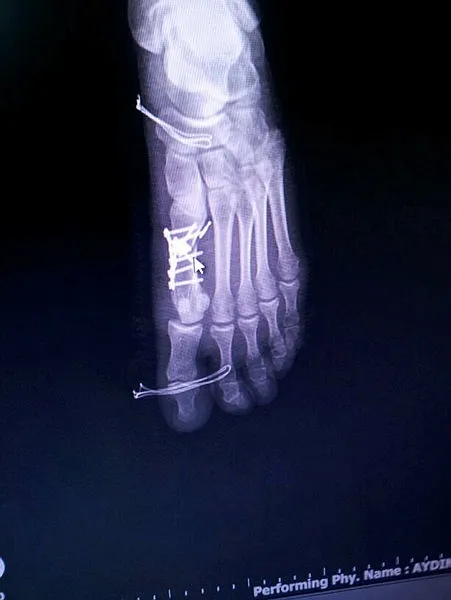

İddiaya göre, İstanbul'da ikamet eden memur Büşra Nergiz, sol ayak parmaklarının birindeki nasır nedeniyle ailesinin yaşadığı Yalova'ya gelerek Devlet Hastanesi Ortopedi ve Travmatoloji Bölümüne müracaat etti ve Opr. Dr. Ö.A. tarafından muayene edildi. Röntgeni çekilen Nergiz'in sol baş parmağının yanındaki parmağında kırık olduğu teşhis edildi. 13 Temmuz'da Ö.A. tarafından aynı hastanede ameliyat edilen Nergiz'in kırık parmağının yerine sağlam sol ayak baş parmağının ameliyat edildiği ve 5 platin takıldığı belirlendi. Bunun üzerine Büşra Nergiz, Cumhuriyet Savcılığına suç duyurusunda bulunurken, şikayet üzerine hastane yönetimi Dr. Ö.A. hakkında idari soruşturma başlattı. Hastaneden önceki gün taburcu edilen ve babasına ait Bağlarbaşı Mahallesi Gelincik Sokak'taki evinde istirahat eden Nergiz, yaptığı açıklamada, ayağındaki rahatsızlık nedeniyle 3 kez aynı hastanede muayene olduğunu söyledi. Ameliyattan sonra kendine geldiğinde yaşadıklarını anlatan Nergiz, şu iddialarda bulundu:

"Yanlış parmağımın ameliyat edildiğini anlayınca durumu yanımdaki aileme söyledim ve doktoru çağırdık. Doktor Ö.A, geldiğinde hangi ayağıma işlem yaptığını dahi bilmiyordu 'Acaba sağ ayağına değil de sol ayağına mı işlem yaptım.' dedi. Bundan bile emin değildi. 'Burada yamukluk gördüm. İstersen gel pazartesi bir daha işlem yapalım.' dedi. Ben de 'Narkoz almıştım zaten, 3 gün sonra tekrardan narkoz almam doğru mu? O zaman ikisini aynı anda yapsaydınız.' dediğimde, o da 'Pazartesi gel istersen yapalım, istersen 6 ay sonra gel bir daha yapalım işlemini.' diye yanıt verdi. Bu şekilde umursamaz bir tavırla çıktı gitti. 4-5 gündür ayağımın üstüne basamadığım için yerimden kalkamıyorum. Ayağıma 5 platin takılmış. Bundan da haberimiz yok. Hastaneden taburcu olduğum gün öğrendim.

Platin takılacağına dair bir şeye imza atmadık. Sormadı. Sağlam ayağıma platin takılması beni yordu. Şu anda ayağıma ne olacağını bilmiyorum. Hasar kalacak mı? Yürümem de herhangi bir şekilde sıkıntı olacak mı? Onu da bilmiyorum." Dr. Ö.A. hakkında savcılığa suç duyurusunda bulunduklarını belirten Nergiz, "Her konuda hakkımızı arayacağız. Davamızın sonuna kadar da arkasındayız. Çünkü bunun cezasız kalmaması lazım. Benim canımı yaktı, başkasının canını yakmasın." diye konuştu. Bu arada, Dr. Ö.A. hakkında hastane yönetimince idari soruşturma başlatıldığı, İl Sağlık Müdürlüğünün de konunun takipçisi olduğu öğrenildi.